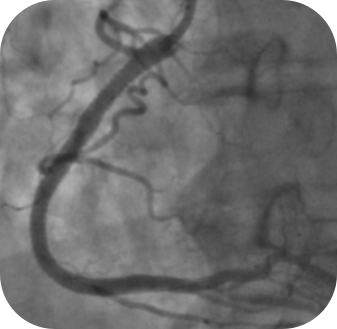

术后造影及OCT图像:术后支架近端及远端贴壁良好,即刻管腔狭窄得以明显改善。

在完成右冠状动脉(RCA)病变的预处理及药物洗脱支架植入后,尽管造影结果提示血流通畅,但为追求更理想的远期预后,团队随即进行了OCT腔内影像学评估。OCT的高分辨率横断面成像清晰显示了支架梁与血管壁的贴壁情况,准确识别出局部存在的贴壁不良。基于此精确反馈,术者选择了合适的非顺应性球囊进行了针对性的后扩张,并经OCT确认支架贴壁得到显著改善,达到了优化的植入效果。